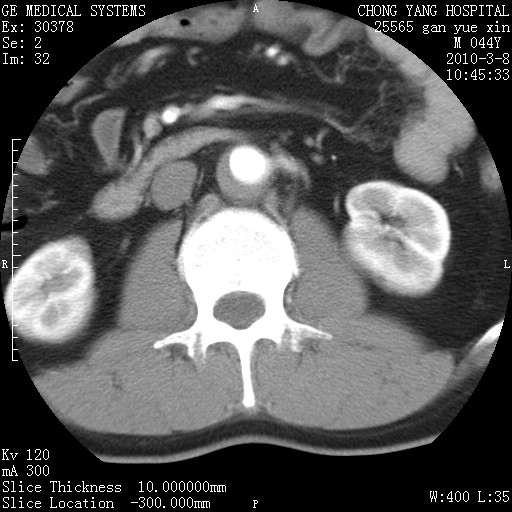

标题: CT24940:主动脉增强,典型病例。 [打印本页]

标题: CT24940:主动脉增强,典型病例。

夹层动脉瘤。

动脉夹层

夹层动脉瘤,典型

主动脉夹层。

动脉夹层的分型:

⒈debakey分型:根据主动脉夹层累及部位,分为三型:ⅰ型:原发破口位于升主动脉或主动脉弓部,夹层累及升主动脉、主动脉弓部、胸主动脉、腹主动脉大部或全部,少数可累及髂动脉。ⅱ型:原发破口位于升主动脉,夹层累及升主动脉,少数可累及部分主动脉弓。ⅲ型:原发破口位于左锁骨下动脉开口远端,根据夹层累及范围又分为ⅲa,ⅲb。ⅲa型:夹层累及胸主动脉。ⅲb型:夹层累及升主动脉、腹主动脉大部或全部。少数可累及髂动脉。

⒉stanford分型:a型:夹层累及升主动脉,无论远端范围如何。b型:夹层累及左锁骨下动脉开口以远的降主动脉。

夹层动脉瘤,少量胸水

夹层动脉瘤;左侧少量胸腔积液。

典型主动脉夹层。